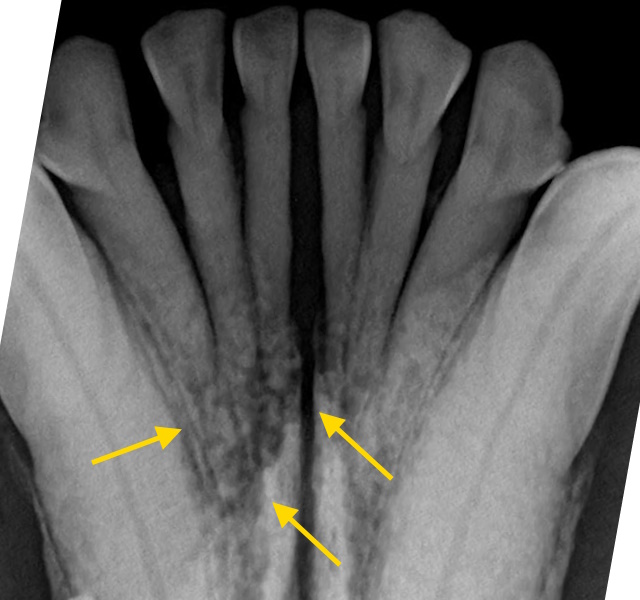

A proliferative, ulcerated and bleeding mass between the lower lips and the lower incisor teeth of a dog.

On dental radiographs, mandibular bone destruction was found around the incisor roots.

Appearance of this patient’s lower jaw immediately after bilateral rostral mandibulectomy.